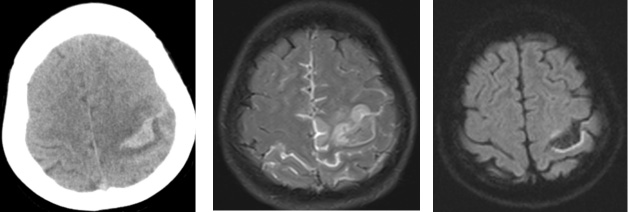

据悉,患者为女性,现年52岁,因“突发剧烈头痛、肢体偏瘫,伴颅内压升高”到新平县总医院北院区就诊,并先后入住新平县总医院北院区急诊医学科和神经内科。鉴于患者入院后,泛静脉窦血栓形成,病情复杂且进展迅速,新平县总医院迅速启动多学科会诊机制,由云南省第一人民医院对口帮扶新平县总医院医疗队驻北院区神经内科专家刘惠牵头,联合驻医学影像科专家陈渝晖,驻急诊医学科专家李娅菲、主管护士杨彦红,驻药学部专家李寅珊、驻超声科专家唐娅玲共同为患者开展救治。在紧张的救治过程中,6名专家充分发挥各自的专业特长,默契配合,有条不紊地为患者开展救治。驻医学影像科专家陈渝晖及时、准确诊断出静脉窦血栓,并指导治疗。同时,动态观察病情,及时调整治疗方案;驻神经内科专家刘惠第一时间识别颅内静脉窦血栓(CVST),并启动抗凝治疗和动态评估神经功能;驻急诊医学科专家李娅菲及时对患者进行抢救,并动态复查头颅CT;驻药学部专家李寅珊及时排查血栓病因,并提供规范用药指导;驻超声科专家唐娅玲为患者完善四肢及心脏B超检查,确保患者生命体征稳定;驻急诊医学科主管护士杨彦红不断加强患者肢体康复护理,预防下肢深静脉血栓形成。在6名专家的全力救治下,患者生命体征恢复平稳,神经功能逐步改善,静脉窦实现再通,脑梗死及出血吸收良好,现已顺利出院。

广泛上矢状窦静脉血栓

静脉性梗死伴出血